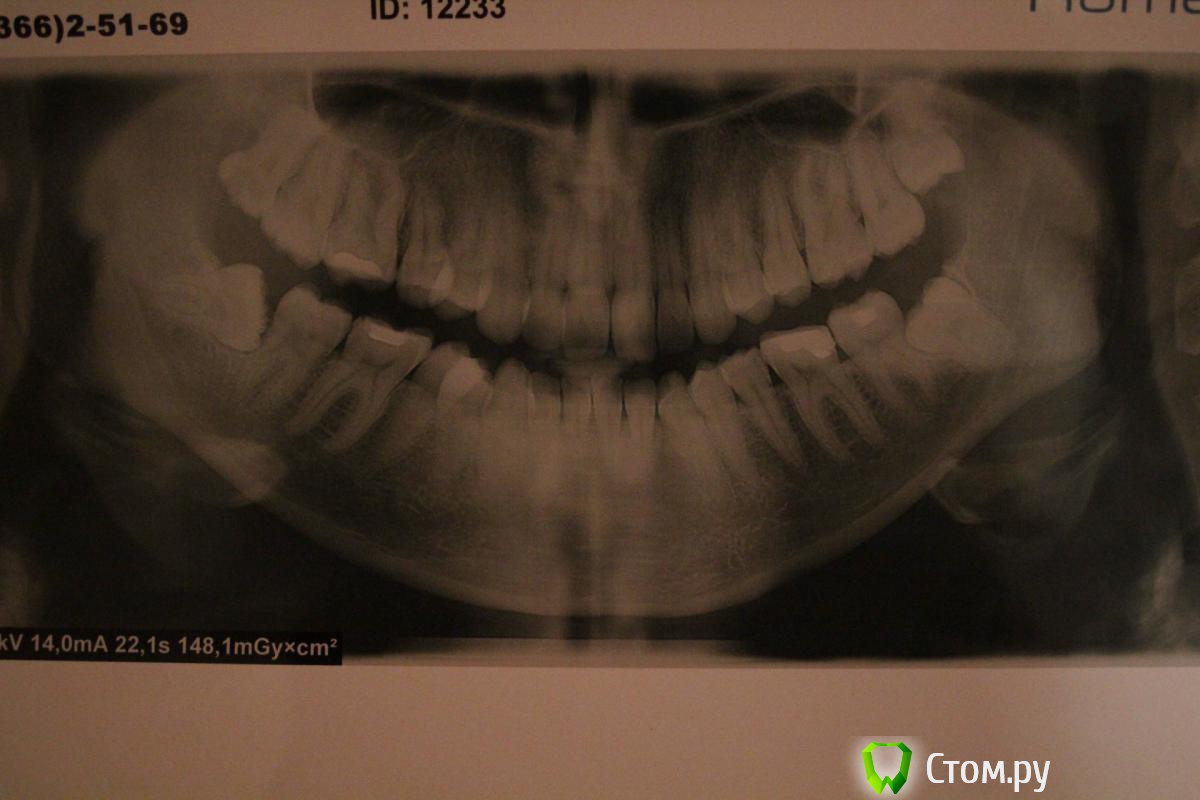

tannja Опубликовано 22 ноября, 2013 Поделиться Опубликовано 22 ноября, 2013 Здравствуйте,посоветуйте, пожалуйста, хирург сказал, что нужно удалить все 4 восьмерки, действительно в удалению нуждаются все зубы? они никогда меня не беспокоили, не болели.мне 27 лет. Ссылка на комментарий

Alexey Doc Опубликовано 22 ноября, 2013 Поделиться Опубликовано 22 ноября, 2013 Здравствуйте.Да, все 4! Ссылка на комментарий

tannja Опубликовано 22 ноября, 2013 Автор Поделиться Опубликовано 22 ноября, 2013 спасибо за ответ! а верхние нужно удалить срочно, один вылез, другой еще нет? Ссылка на комментарий

IvanK Опубликовано 22 ноября, 2013 Поделиться Опубликовано 22 ноября, 2013 спасибо за ответ! а верхние нужно удалить срочно, один вылез, другой еще нет?Верхние можно позже. Ссылка на комментарий